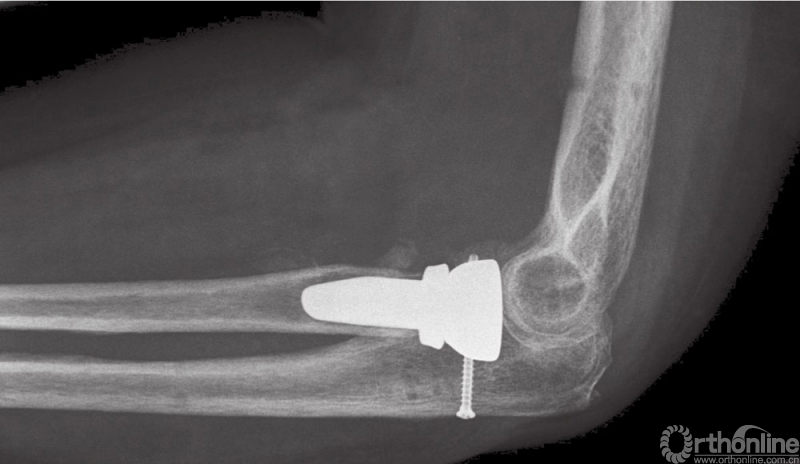

图9 (与图2为同一患者)使用铰链式外固定支架后的术后侧位X线片

图11 长期随访患者,侧位片显示关节复位满意